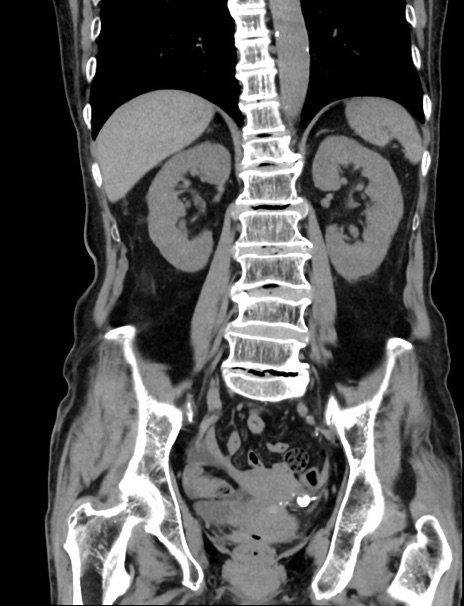

症例33(冠状断像)

【症例】70歳代 女性

【主訴】心窩部痛

【現病歴】延髄病変の精査・加療にて神経内科入院中。本日より心窩部痛あり。

【身体所見】右下腹部を中心に圧痛と反跳痛あり。

【データ】WBC 10900、CRP 0.02